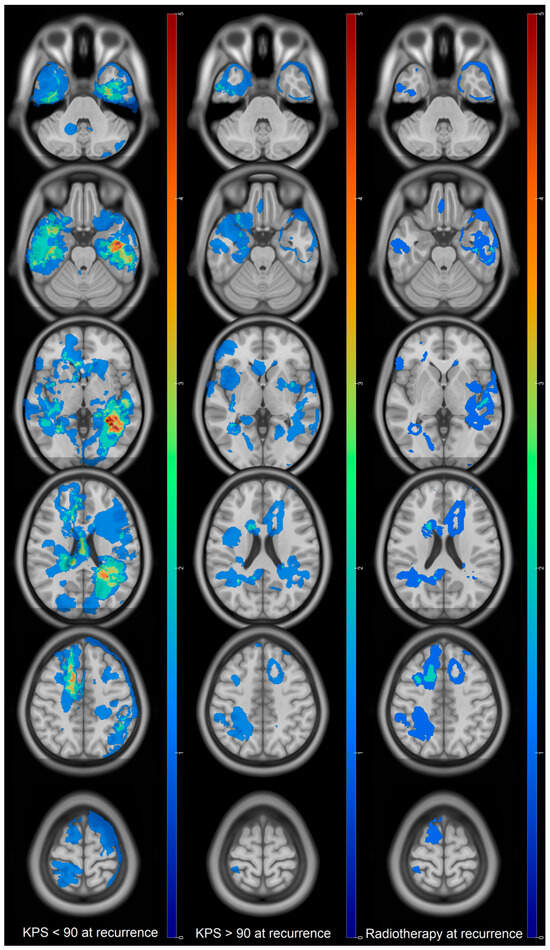

Prognostic Factors of IDH Wild-Type Glioblastoma After Extensive Surgery: A Multimodal Atlas of Tumor Locations, Recurrences and Management

by Hajar Selhane, Tiphaine Obara, Guillaume Vogin, René Anxionnat, Guillaume Gauchotte, Luc Taillandier, Marie Blonski and Fabien Rech

Cancers 2026, 18(1), 63; https://doi.org/10.3390/cancers18010063 - 24 Dec 2025

Introduction: Glioblastomas have poor prognosis despite aggressive treatment. Patterns of recurrence and overall survival (OS) can be very different. The population with complete resection having a so-called good prognosis can nevertheless present poor OS. Our purpose was to assess the OS and patterns [...] Read more.

Introduction: Glioblastomas have poor prognosis despite aggressive treatment. Patterns of recurrence and overall survival (OS) can be very different. The population with complete resection having a so-called good prognosis can nevertheless present poor OS. Our purpose was to assess the OS and patterns of recurrence thanks to multimodal statistical maps in glioblastoma with large extent of resection (residue < 10 mL). Methods: adult patients presenting IDH wild-type glioblastoma between 2013 and 2019 were selected. Clinical data and MRI characteristics were collected. Preoperative, postoperative, and recurrence volumes were segmented and normalized in the MNI space to compute statistical maps. Log-rank test and Cox model were used to assess OS and prognosis factors. Results: 60 patients were included. Mean residual volume was 0.89 ± 2 mL. Median OS was 22.3 months (95% CI: (20–35)). Initial location in the corpus callosum was associated with low OS (317 vs. 783 days, HR = 0.46, p = 0.003). At recurrence, KPS > 90 and tumor volume < 10 mL were associated with higher OS (p =0.006 and p = 0.05). Tumor contact with the SVZ as well as multifocal recurrence did not show any impact on the OS. Conclusions: High OS can be obtained thanks to surgery with residual volume < 10 mL. Invasion of the corpus callosum at diagnosis is associated with a poor prognosis despite a large extent of resection. Results suggest that large resection near the SVZ might decrease its putative influence on OS. Full article

Figure 1